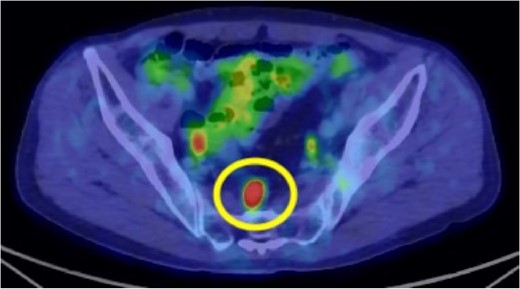

A 72-year-old man diagnosed with NSCLC was referred for possible surgical treatment of a solitary nodule detected in the mesorectum. His medical history included hypertension and endoscopic resection of colonic polyps, with no prior thromboembolism. He had received combined medical treatment for NSCLC (cT4N0M0, stage IIIA) (Fig. 1), including four courses of cisplatin and docetaxel chemotherapy with a 60 Gy/30 fractions radiation dose, followed by 1 year of consolidation therapy with durvalumab (640 mg/body). The patient tolerated the treatment well, achieving a complete response 13 months before presentation (Fig. 2). However, the mesorectal nodule was incidentally discovered during surveillance CT after NSCLC treatment completion. It was round, 15 mm in diameter, showed contrast enhancement, and was near the mesorectal vessels (Fig. 3a and b). An FDG PET/CT scan revealed a solitary mesorectal nodule with an SUVmax of 10.3 (Fig. 4). Consequently, the radiologist suggested differential diagnoses of malignant lymphoma and metastatic lymph nodes from the urinary or lower gastrointestinal tract, as NSCLC typically does not metastasize to mesorectal lymph nodes. No other abnormal FDG uptake was observed. Laboratory tests showed normal levels for tumor markers, including carcinoembryonic antigen, sialyl Lewis X (SLX), squamous cell carcinoma antigen, neuron-specific enolase, cytokeratin fragment (CYFRA), progastrin-releasing peptide, and blood coagulability was within the normal range. Total colonoscopy revealed no neoplastic lesions, and urinary cytology showed nonmalignant urothelial cells. Noninvasive diagnostic approaches, including endoscopic or CT-guided biopsy, were extensively discussed but deemed difficult because of anatomical restrictions, risk of dissemination, and procedure-related complications (such as bleeding or perforation). Because of the potential malignancy and need for en-bloc resection, we opted for surgical resection using a standardized laparoscopically assisted mesorectal excision technique. During rectal dissection, the nodule was not visible through the posterior and lateral sides because it was completely embedded in the mesorectum. Therefore, a Pfannenstiel incision was made in the lower abdomen to exteriorize the rectum after the division of the proximal colon. The nodule was confirmed by direct palpation, marked with a stitch, and subsequently removed after intracorporeal transection of the distal rectum. We inspected the resected specimen and confirmed that the nodule was incorporated (Fig. 5a and b). A colorectal anastomosis was then performed using a double-stapling technique with a circular stapler. The postoperative course was uneventful, except for a slight elevation of the d-dimer level (up to 3.26 μg/ml) on postoperative Day 7, which normalized spontaneously without intensive anticoagulation therapy. The patient was discharged on postoperative Day 10. Pathological examination revealed that the 7-mm white nodule was an intravenous organized thrombus in the mesorectum surrounded by granulation tissue, with no malignancy observed (Fig. 6a and b). Postoperatively, the patient did not require additional chemotherapy or anticoagulation therapy. During the 16-month follow-up, no radiological evidence of NSCLC recurrence and thromboembolism was detected (Fig. 7).

Preoperative 18F-fluorodeoxyglucose (FDG) positron emission tomography (PET)/computed tomography (CT) image. The circle highlights the nodule located in the mesorectum with a maximum standardized uptake value (SUVmax) of 10.3.